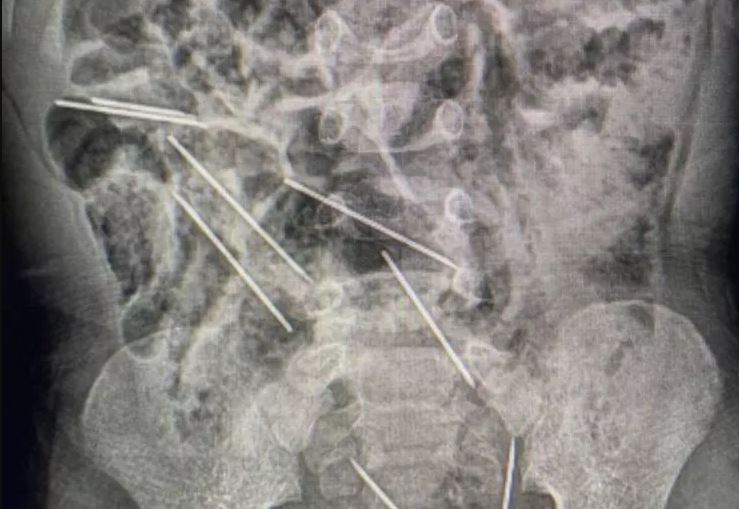

طفل يبتلع 8 إبر حقن مخصصة للحيوانات وتدخل عاجل من الأطباء

أنقذ أطباء في شمال شرق بيرو حياة طفل عمره عامين بعد أن ابتلع ثماني إبر حقن وهو يلعب.

وقال الطبيب إفراين سالاسار "عندما كنا في غرفة العمليات وفتحنا بطنه وجدنا تلك القطع المعدنية، (وأدركنا) أنها كانت في الحقيقة إبرا".

وذكرت وسائل إعلام محلية أن الإبر كانت من تلك التي تستخدم لتطعيم حيوانات بمزرعة تعمل فيها والدة الطفل.